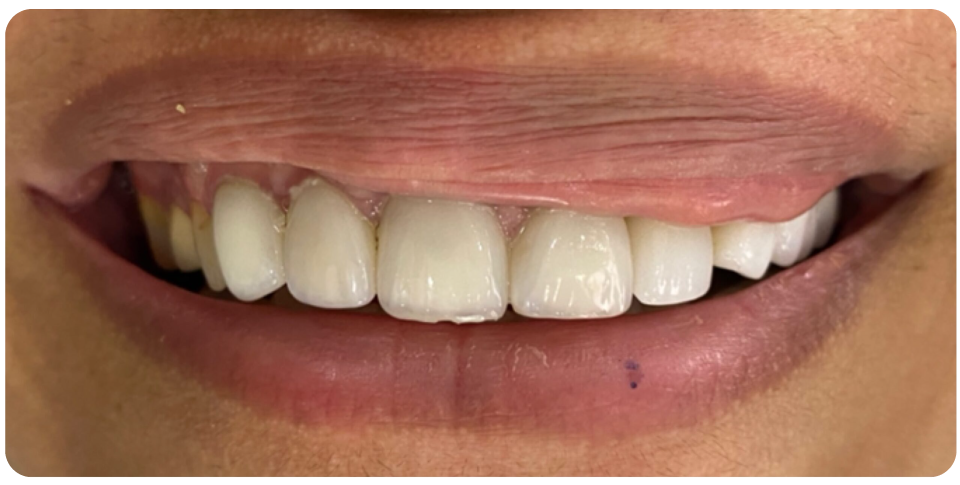

An implant-supported bridge is an excellent solution for replacing multiple missing teeth without relying on natural teeth for support.

Instead of traditional bridges that require grinding down adjacent teeth, this option uses dental implants as a strong and permanent foundation.

Benefits of Implant-Supported Bridges:

- Stronger & More Stable – Provides better support and durability than traditional bridges.

- Preserves Jawbone Health – Prevents bone loss by stimulating the jawbone.

- No Damage to Natural Teeth – Adjacent teeth remain intact, unlike traditional bridges.

- Enhanced Function & Aesthetics – Restores chewing ability and a natural-looking smile.

Ideal for multiple missing teeth, implant-supported bridges offer a long-lasting and comfortable solution for restoring your smile.